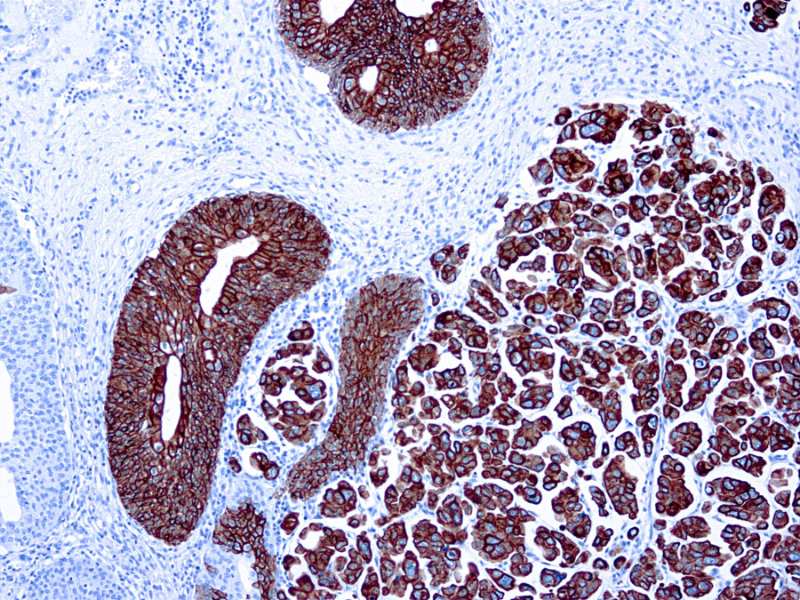

Cytokeratin 7 rmab 063 carincoma Published February 20, 2021 at 800 × 600 in Cytokeratin 7 rmab 063 carincoma Cytokeratin 7 rmab 063 carincoma Cytokeratin 7 rmab 063 carincoma ← Previous Next →